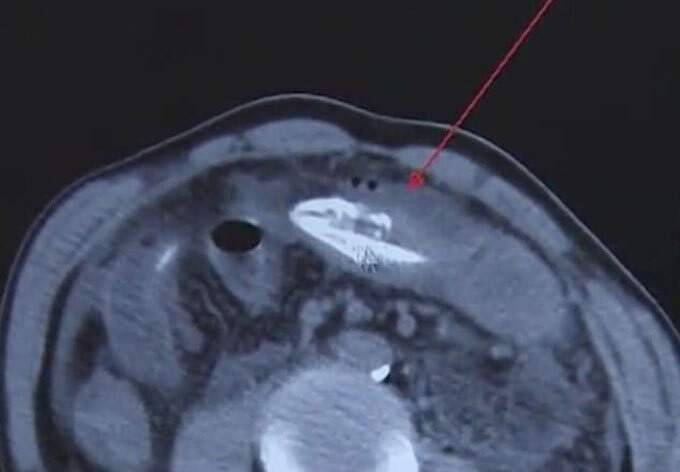

Gần đây các bác sĩ ở một bệnh viện tại Hình Hoa, tỉnh Giang Tô đã phẫu thuật để lấy một con lươn còn sống khỏi bụng của một nam bệnh nhân.

Theo các bác sĩ, nếu việc phẫu thuật chậm trễ, người đàn ông này có thể chết vì tan máu - gây ra do vi khuẩn trong ổ bụng, phá huỷ các tế bào hồng cầu.

Tin tức được lan truyền sau khi nam bệnh nhân tìm đến bệnh viện do đau bụng dữ dội. Ban đầu, ông này bị táo bón nhưng không đi khám vì ngượng ngùng. Để tự chữa bệnh ở nhà, ông này thực hiện phương pháp dân gian, nhét một con lươn vào cơ thể theo đường hậu môn.

Ông này tìm đến Bệnh viện Hoàng Giang, thành phố Đông Quan, tỉnh Quảng Đông sau khi cũng cảm thấy đau bụng dữ dội. Khi các bác sĩ mổ lấy con lươn ra, họ cho biết nội tạng của nam bệnh nhân bị nhiễm trùng nặng và chứa đầy chất thải.